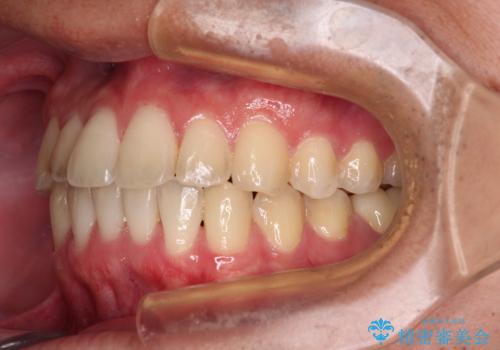

- 前歯のクロスバイトを気にして来院された患者様です。

骨格的には問題がなかったため、インビザラインを用いて咬み合わせを改善していくこととしました。

インビザライン特有の、奥歯の咬み合わせの問題もなく、しっかりと歯列を改善することができました。

舌側転位している上顎側切歯(内側に引っ込んでいる真ん中から2番目の歯)は、インビザラインが最も移動を苦手とする歯であり、これ以上の改善を望まれる場合にはワイヤー矯正、あるいはワイヤー矯正の併用をお勧めいたします。